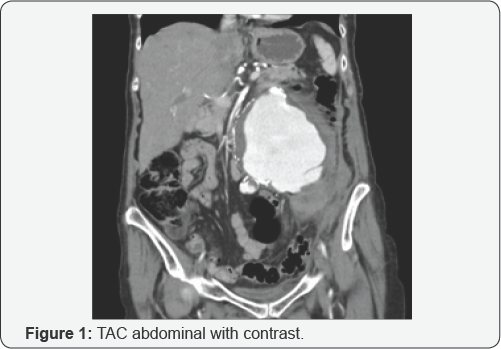

80-year-old female patient with 12cm infra-renal abdominal aortic aneurysm (Figure 1 & 2) complicated with lumbar pain and anemia was admitted (Hb: 7.7mg/dl). In addition, there was kidney function deterioration (creatinine: 1.51mg/dl) due to compression of the left ureter and pyelo-calyx dilatation (Figure 3).